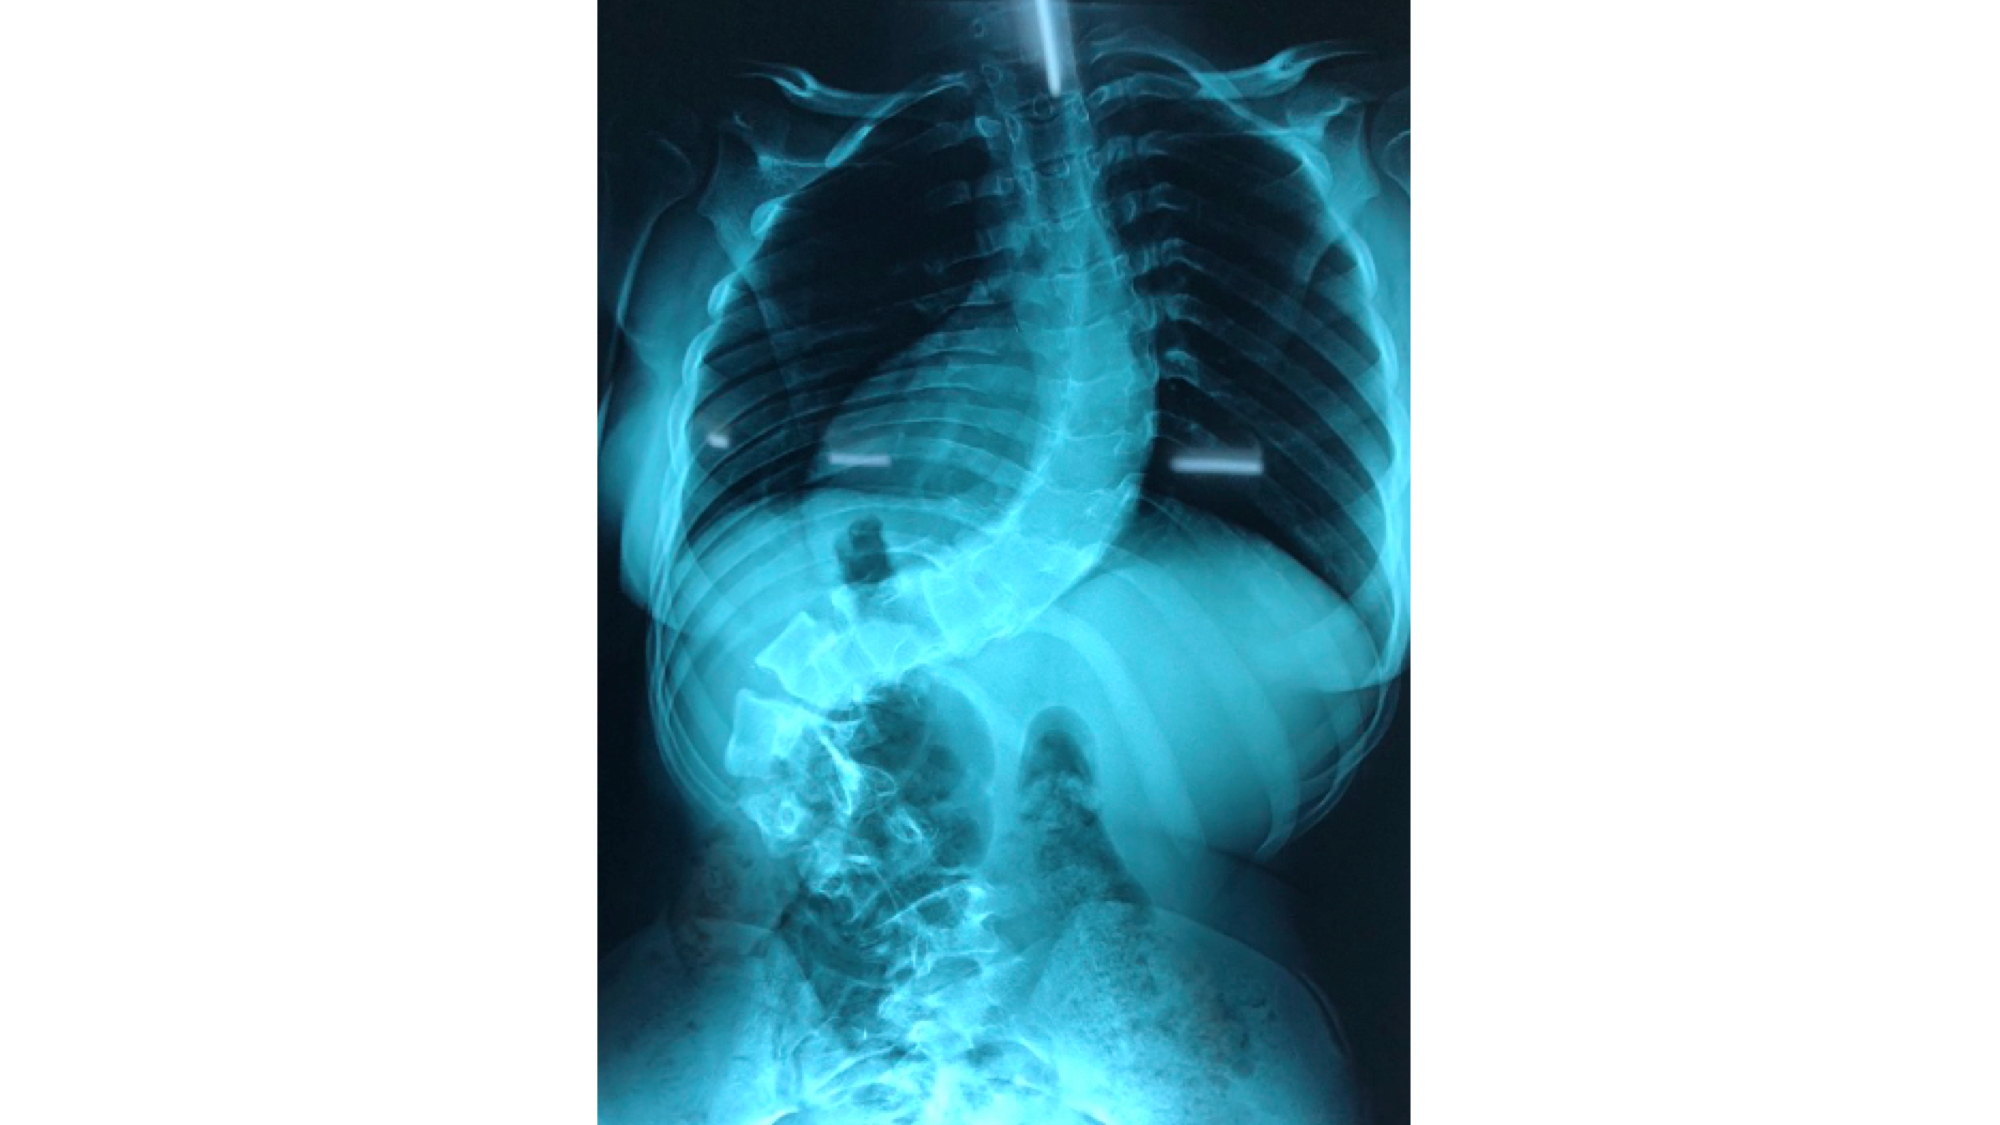

I was also able to meet the first two spine surgery fellows at AaBET. They are both neurosurgeons. The plan after next year is to alternate orthopedic with neurosurgery spine fellows. In addition to their teaching at AaBET, they are mentored by Dr Fasil Mesfin of Univeristy of Missouri, with whom they have weekly cases conferences. They were excited to show me two massive spine tumors they just operated on, one a giant, dumbbell shaped neurofibroma of the lower thoracic spine with bone involvement and preoperative paraparesis; the other a huge aneurysmal bone cyst of posterior lumbar element. Both needed pedicle screw instrumentation and big exposures. I am not a spine surgeon but the operative photos and postop xrays were very impressive.